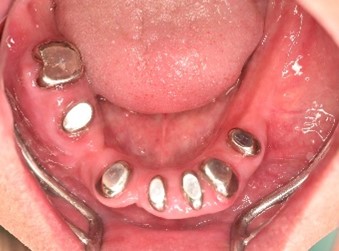

Before

赤丸は抜歯しました。上4本、下3本